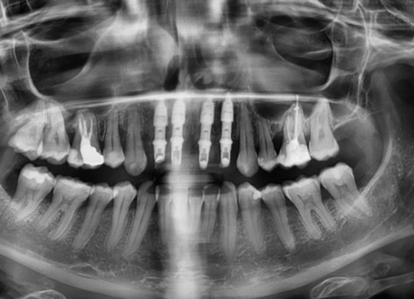

Riabilitazione del settore anterosuperiore con sistema modulare GTB + GFA

Il processo alveolare e il periodonto sono strutture anatomiche tooth-dependent; infatti, la perdita di un elemento dentario è seguita da una reazione a cascata di fenomeni biologici che causano un’atrofia progressiva dei tessuti parodontali sia duri che molli. Quest’ultima è caratterizzata da un lato da una perdita totale delle fibre di inserzione del cemento radicolare, del legamento parodontale e del bundle bone, e dall’altro da un’alterazione volumetrica in senso verticale e orizzontale. Si è visto che il riassorbimento della cresta alveolare, con il suo conseguente riposizionamento linguale, può arrivare ad essere del40-60%, e che tale fenomeno si produce in massima scala nei primi 3-6 mesi seguenti all’ estrazione dentale, ma persiste anche gradualmente durante tutta la vita dell’individuo (circa 0.5-1% ogni anno).Nello specifico, durante le prime otto settimane, si produce un riassorbimento osseo soprattutto nella zona medio-vestibolare, cioè quella anatomicamente meno prossima al legamento parodontale dei denti adiacenti(se esistenti), che aiutano a mantenere l’osso interprossimale . Inoltre, in un biotipo sottile, il difetto generato sarà un difetto a due pareti, a causa della perdita più o meno consistente della corticale vestibolare; mentre sarà a tre pareti nei biotipi spessi, grazie al maggior spessore della corticale esterna.